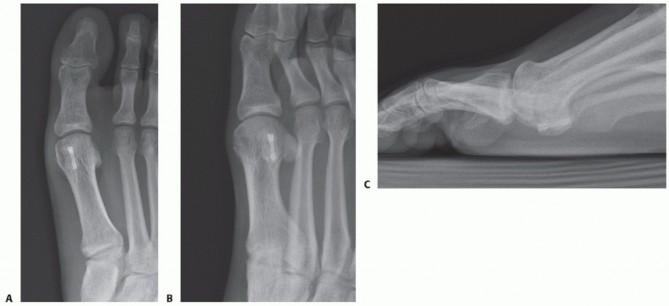

Radiographs suggest medial (tibial) sesamoid fracture (TECH FIG 3A,B).

CT scan demonstrates transverse fracture line with a subacute/chronic appearance (TECH FIG 3C). - Exposure

- TECH FIG 3 • A 22-year-old man with right medial (tibial) stress fracture failing to heal with nonoperative measures. A. AP view. Note medial (tibial) sesamoid with a gap and slight hallux valgus. B. Sesamoid view does not demonstrate this fracture. C. CT scan demonstrates transverse fracture line with a subacute/chronic appearance.